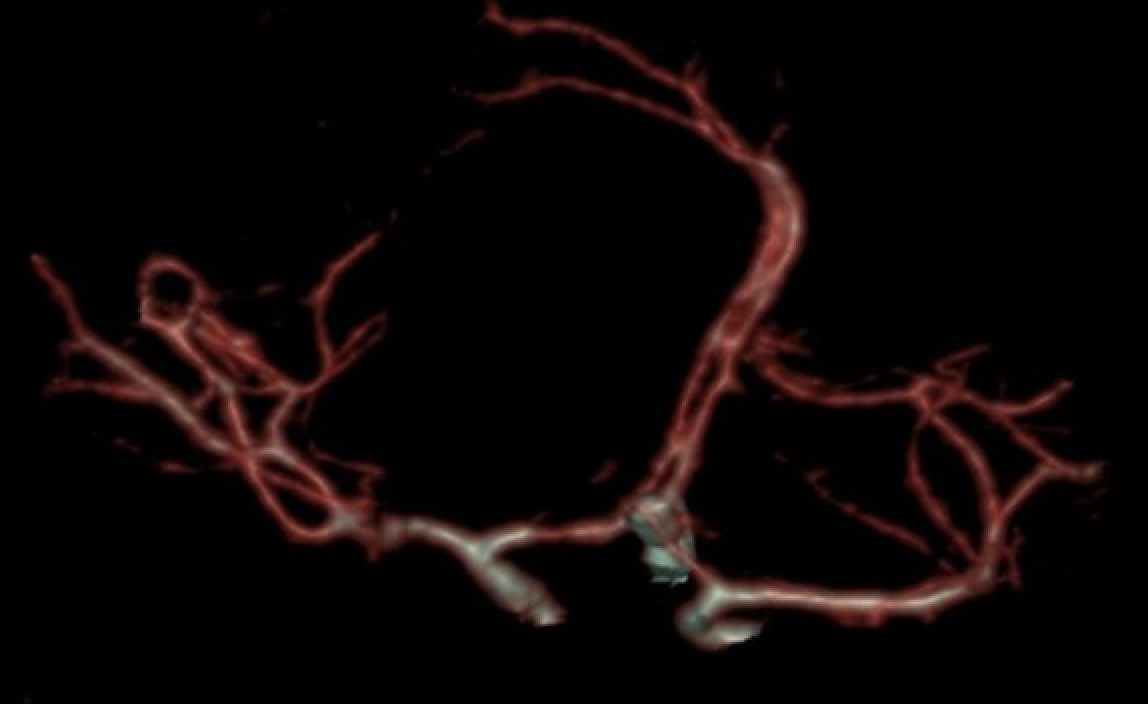

术后影像

颅内动脉瘤的精准夹闭

患者术后神经功能正常